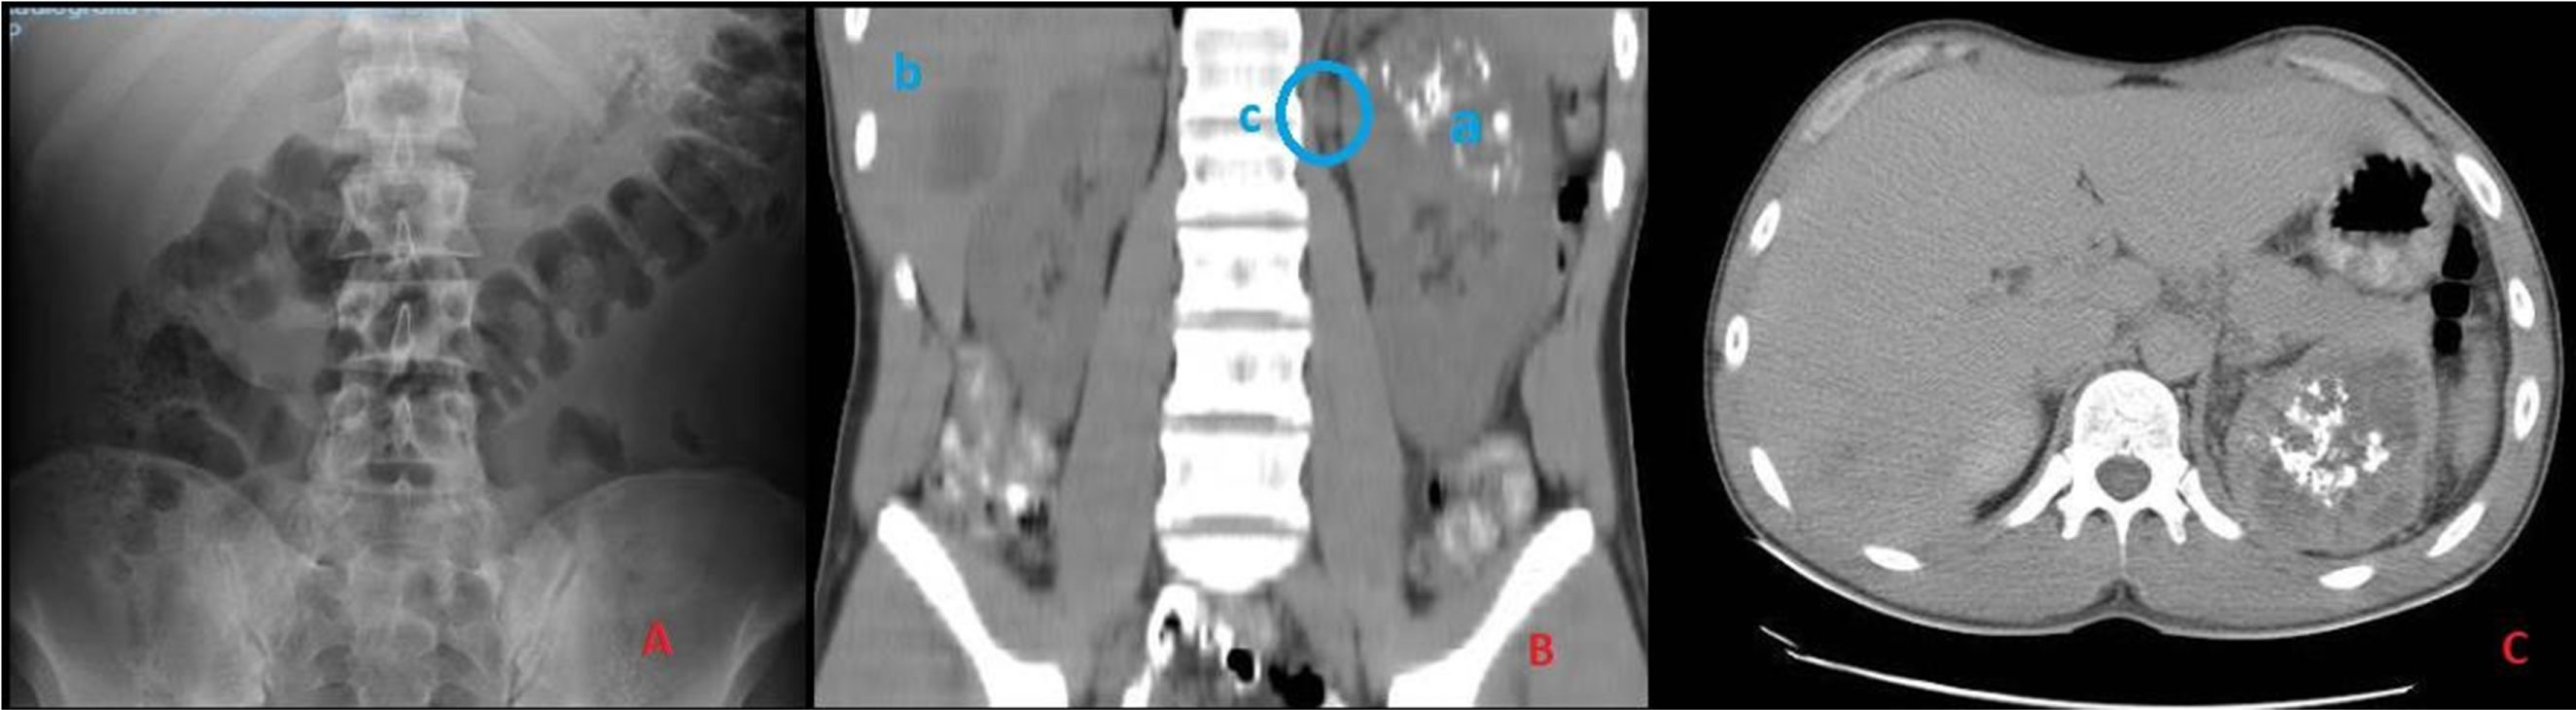

The abdominal X-ray showed a heterogeneous, calcified, poorly delimited image of 5 cm in the left hypochondrium (Figure 1). Tumoral markers, and hepatic-renal profiles were normal on blood test. CT scan showed a heterogeneous and calcified left renal mass, sized 12 × 7.6 cm, dependent on the upper pole, with no vascular invasion. Left hiliar and para-aortic adenopathies, up to 3 cm were also reported. Moreover, a 4 × 3.6 cm hypodense lesion in the 6th hepatic segment, and another one, 12 mm, in the hepatic dome, compatible with metastasis, were described (Figure 1).